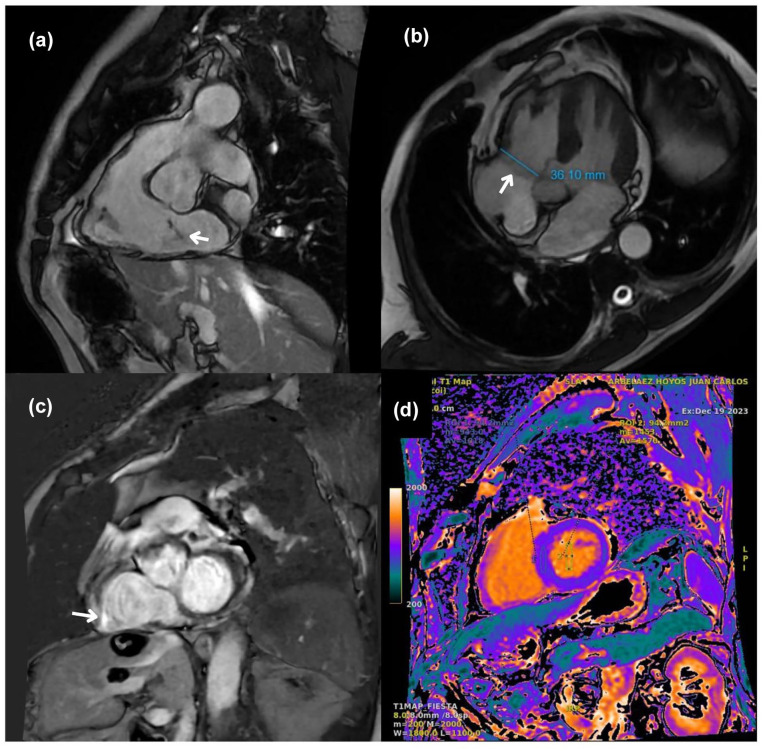

Case: A 68-year-old male with atrial flutter, coronary artery disease, and type 2 diabetes underwent cavotricuspid isthmus ablation in August 2023 after failed rate control. By September 2023, he developed a grade 4/6 systolic murmur. Imaging confirmed TVP with mild to moderate TR, though he remained asymptomatic. Conservative management was adopted. Follow-up in October 2024 showed mild TR without prolapse, indicating improvement.